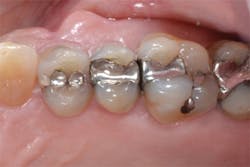

Figure 12: Final preparations on teeth Nos. 4 and 5. The Palodent Plus Sectional Matrix System has been used to isolate the MOD prep on tooth No. 4 and MO prep on tooth No. 5. The Palodent Plus Sectional Matrix System can be configured to restore multiple surfaces and multiple teeth in the same quadrant.

Figure 13: View of teeth Nos. 4 and 5 after curing the final occlusal layer of TPH Spectra composite.